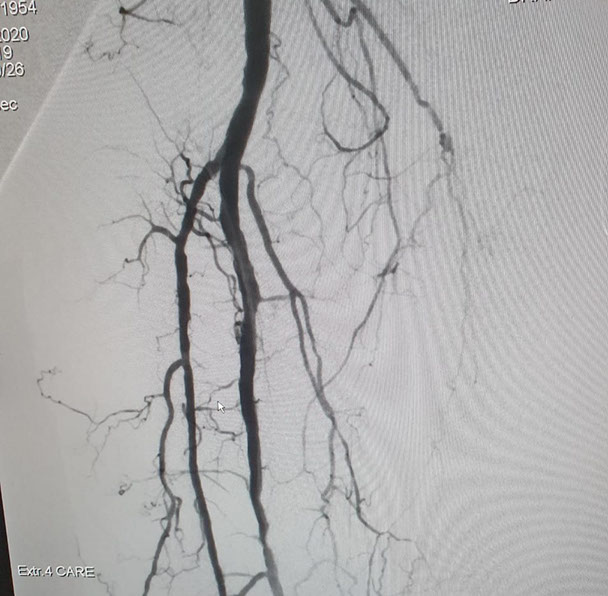

El Dr Sergio Raul Ludueña Jefe del Servicio de Hemodinamia de INCOR nos comentó sobre procedimiento realizado en el día de ayer en en el Servicio. "Queremos compartir con ustedes si bien no es un caso coronario , es un paciente obeso mórbido, diabético, con amputación supracondilea de miembro inferior izquierdo hace 3 años y actualmente con isquemia critica de miembro inferior derecho, con oclusión de ambas tíbiales y sin circulación en el pie".

Se realizó un abordaje híbrido con el Dr. Alejandro Flores, y se re canalizó ambas arterias tíbiales. Procedimiento inédito en nuestra provincia.

Las imágenes siguientes son previas al procedimiento y posterior se ve ambas arterias tíbiales permeables, y circulación en el pie